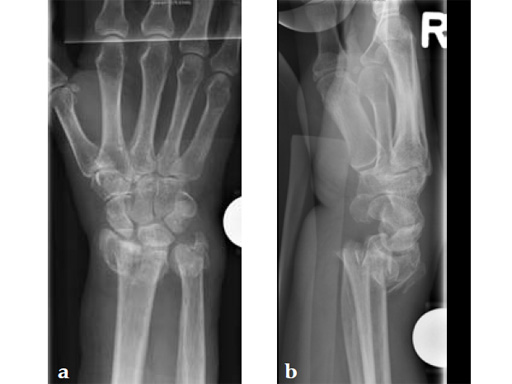

Fig 2ab Initial management was with closed reduction and joint bridging external fixator. There was loss of primary reduction due to inadequate positioning of the external fixator (too lateral).